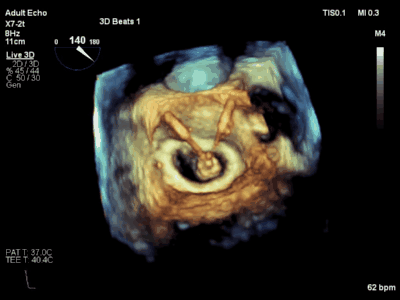

下图1是AMEND手术的其中一位心肌梗死后缺血性心肌病合并功能性重度二尖瓣反流的老年男性患者,心功能差,左室射血分数仅35%,反流面积接近10cm2。术前食道超声评估该患者二尖瓣瓣叶,腱索等结构并无明显异常,二尖瓣环明显扩张,诊断为功能性二尖瓣重度反流。

图1 术前超声